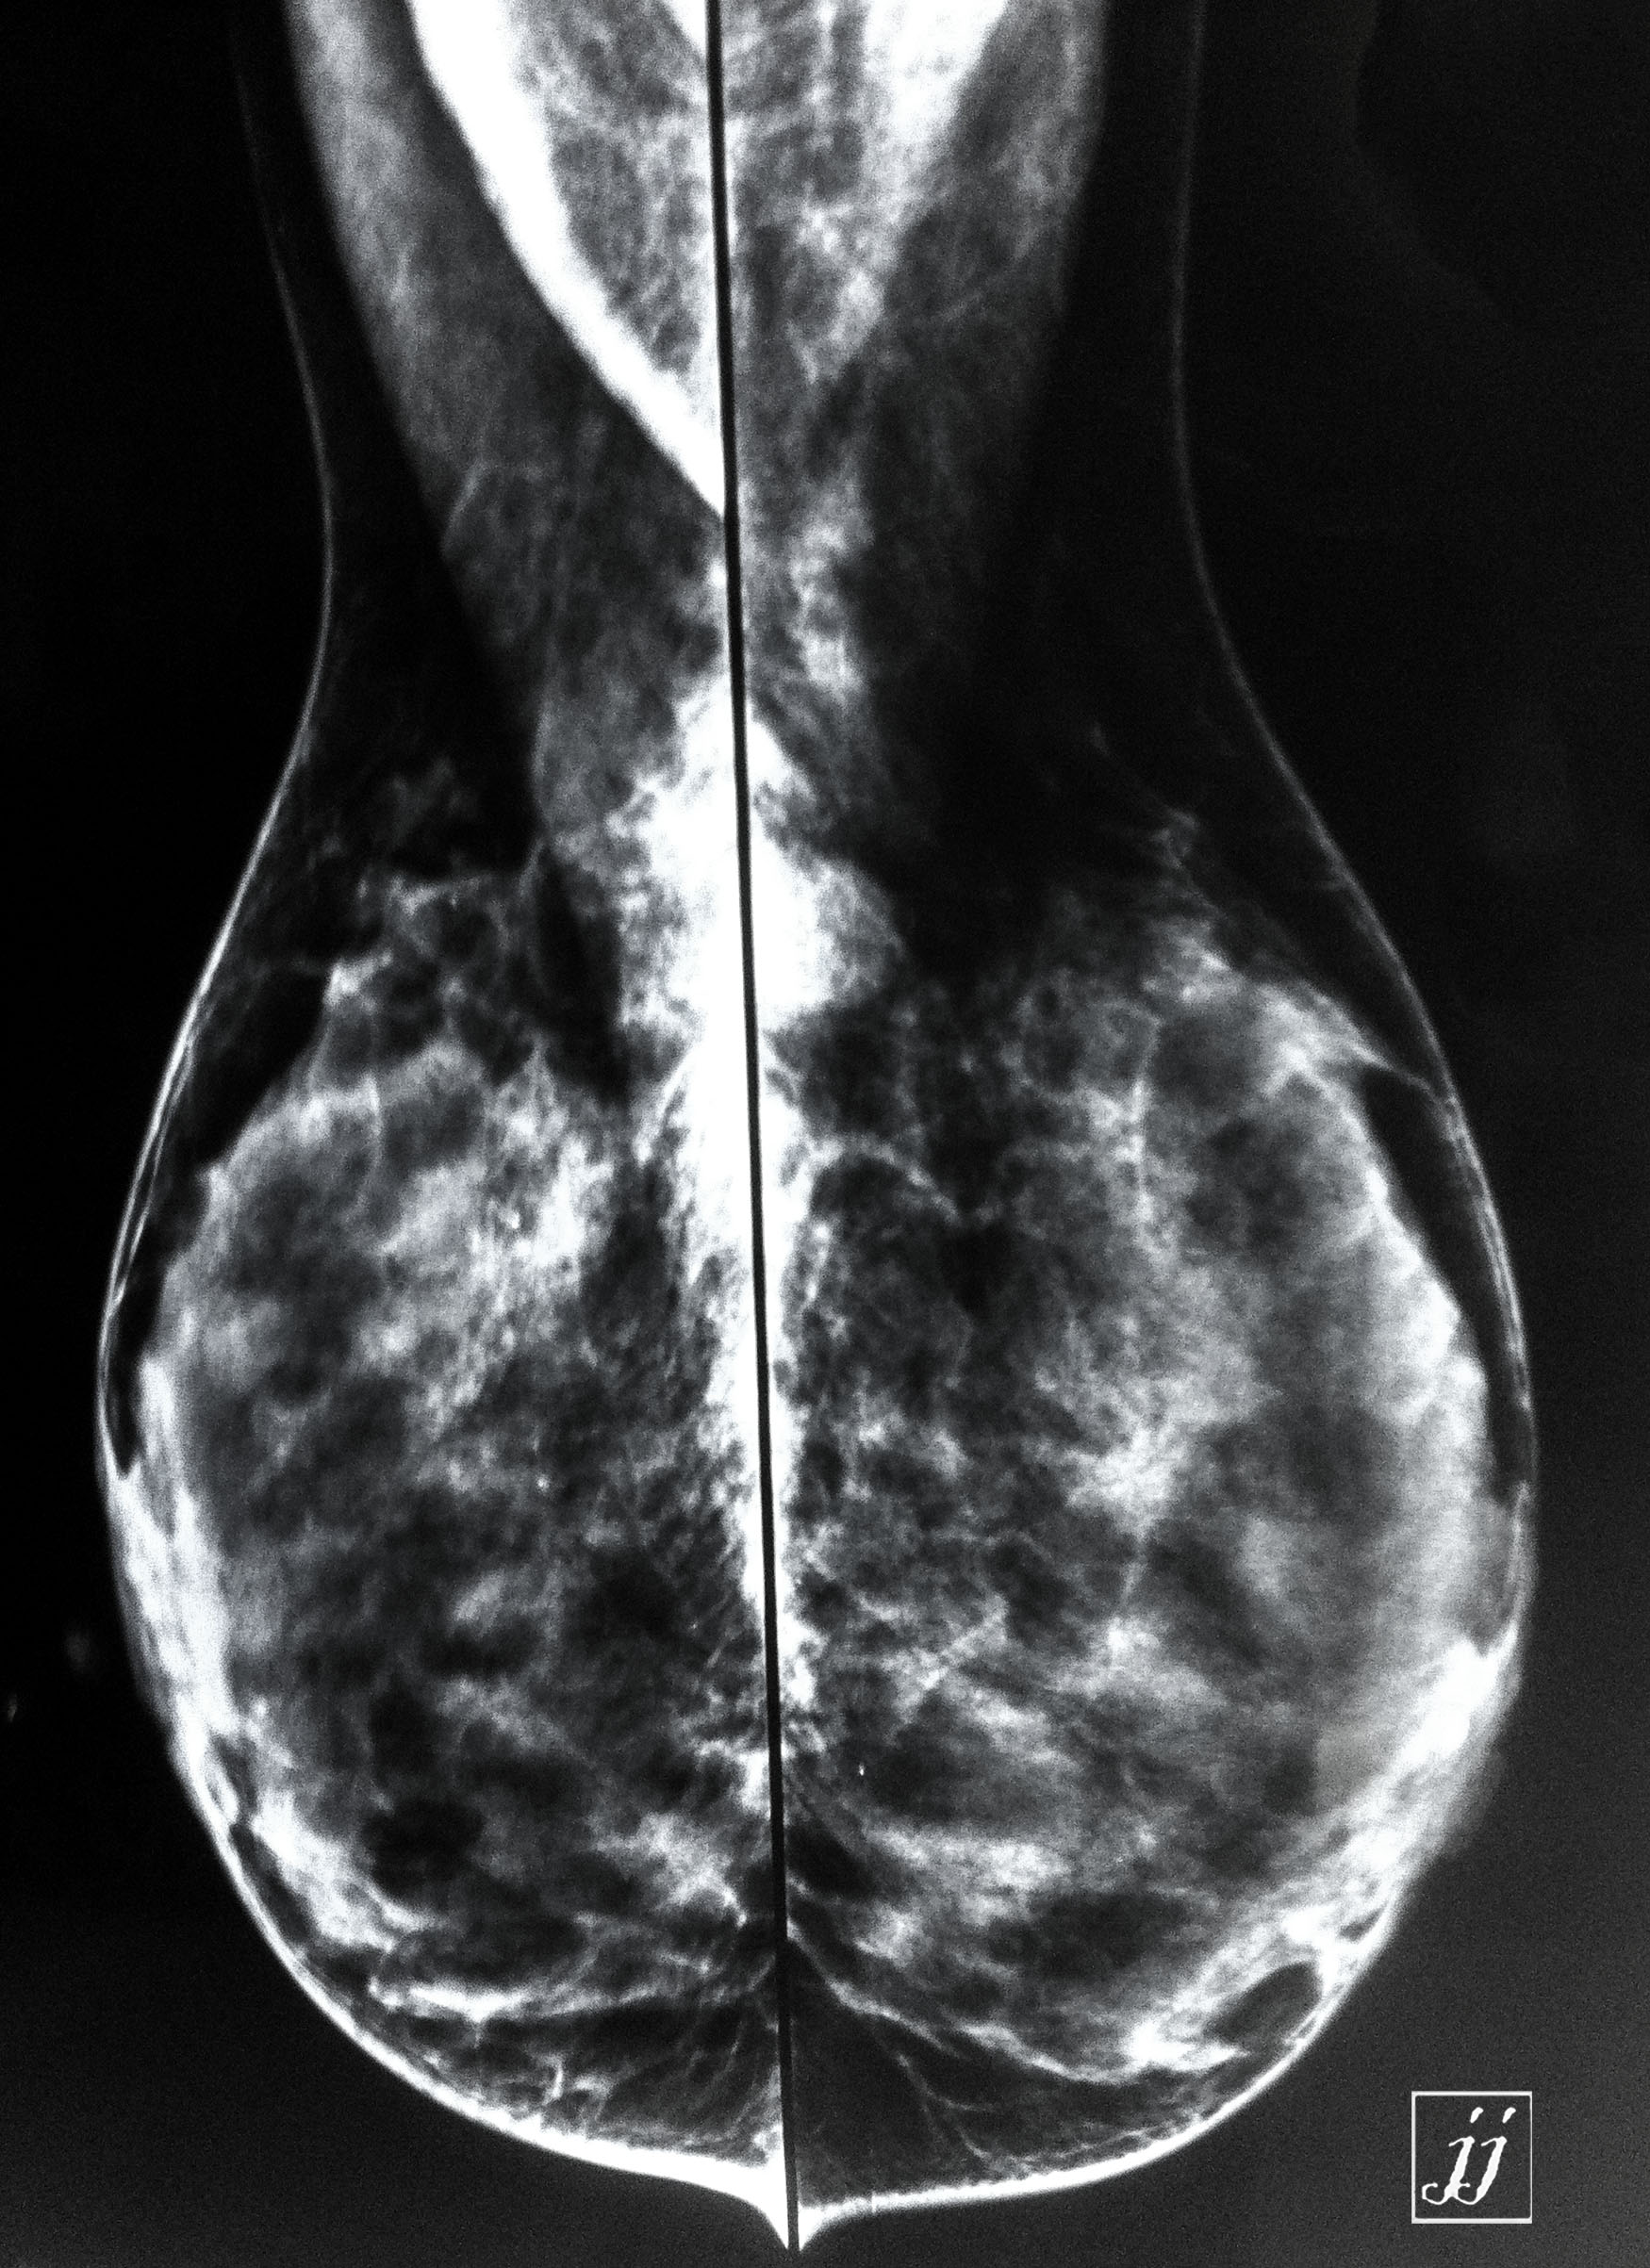

Breast- breast cyst (3)